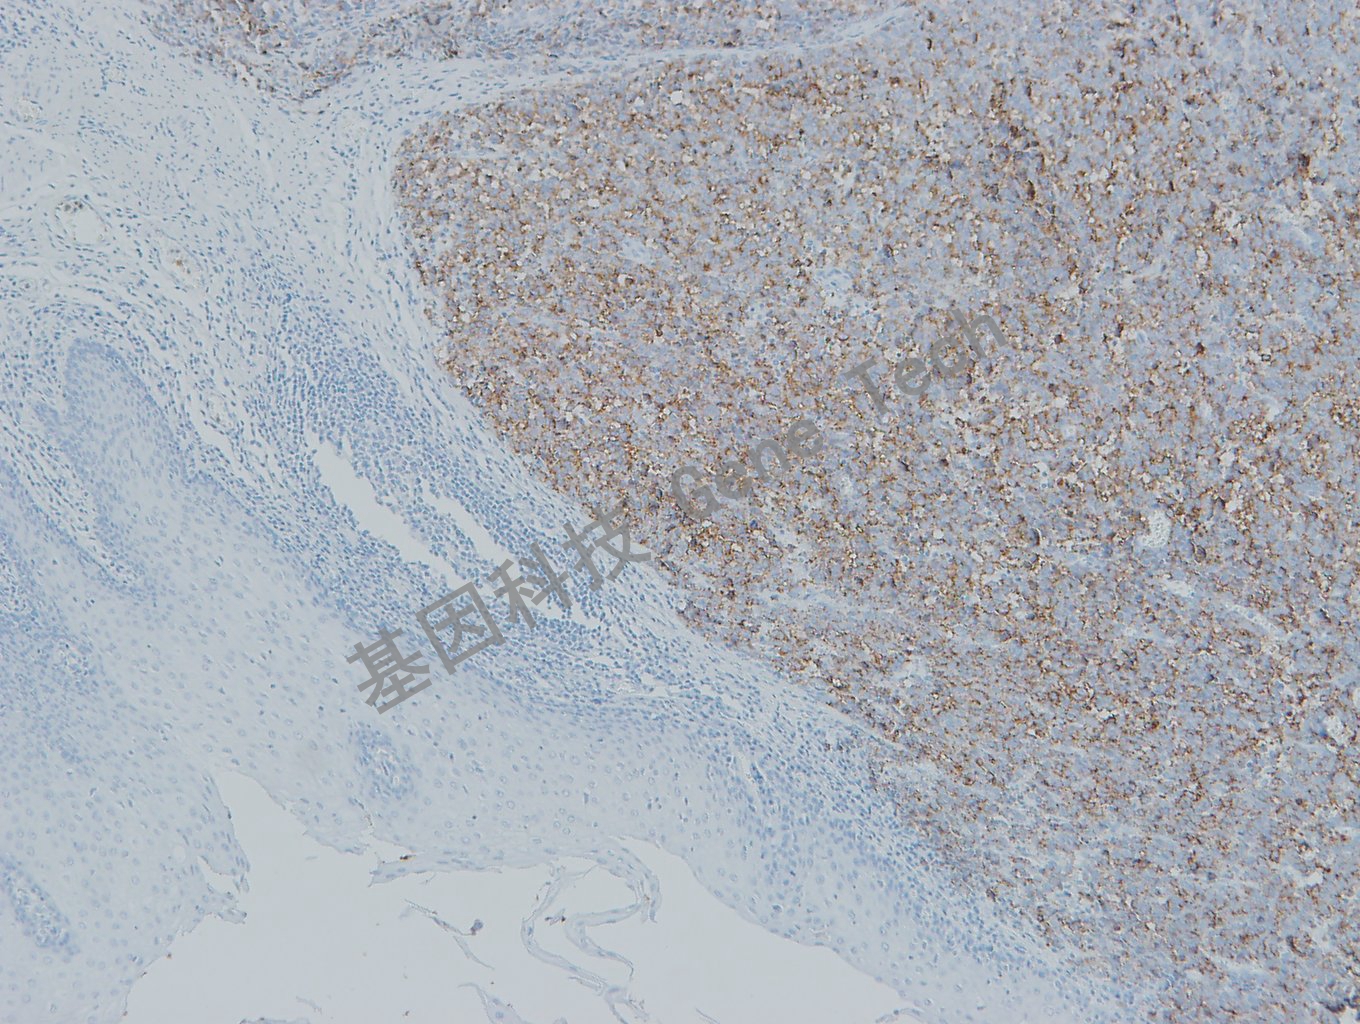

黑色素瘤石蜡切片,用 PNL2(GT2336)染色,细胞浆阳性,DAB 显色。